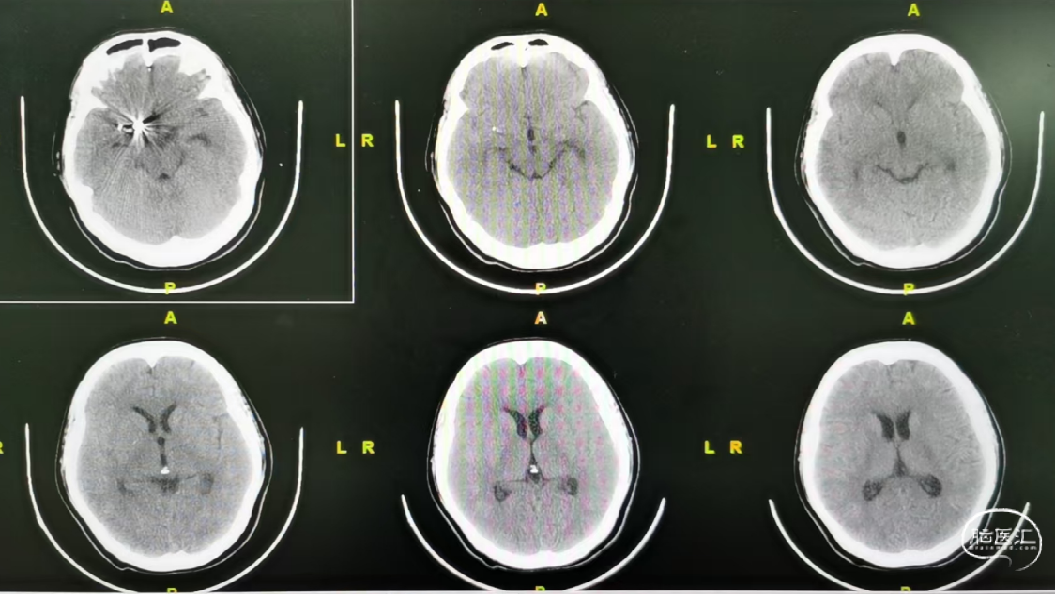

术后2周复查:

复查CT:SAH吸收

术后半年随访: